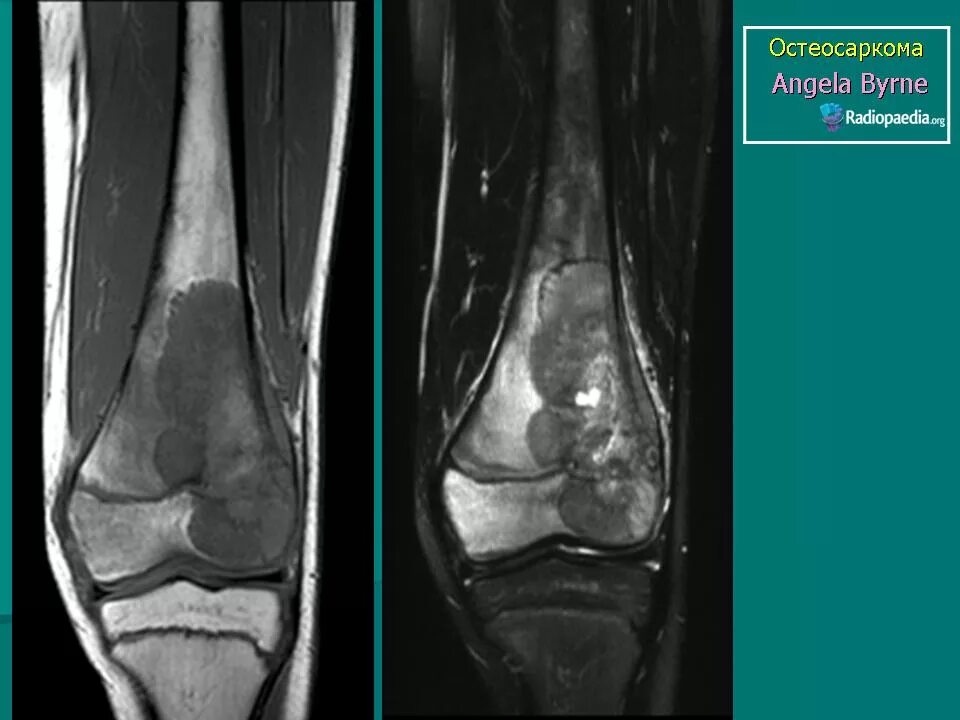

Саркома мрт